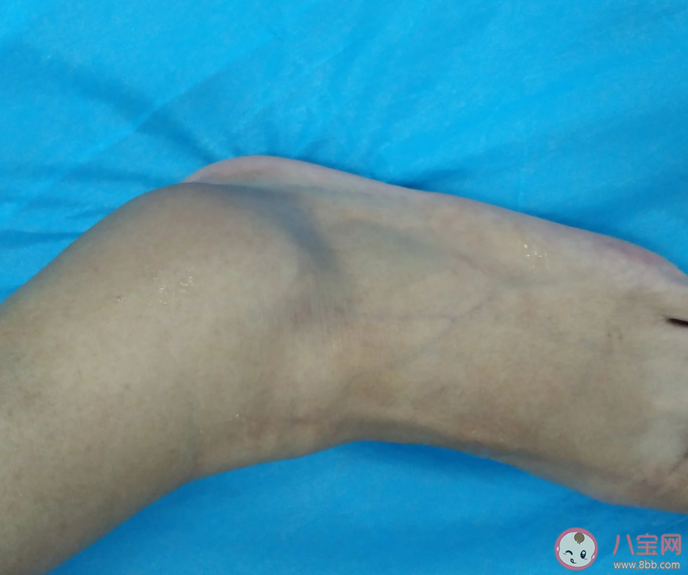

崴腳,在醫學上有個專業名詞,叫“踝關節扭傷”。它的發病率極高,據相關數據顯示,我國平均每天約有30萬人因為崴腳就診,而每個人一生中至少發生過1-2次的崴腳,可見其普遍性。

踝關節扭傷是最常見的運動系統損傷性疾病,其中超過85%的患者屬于內翻暴力造成的外踝韌帶損傷。在初次外踝扭傷后,如果未能正確處理,導致損傷后的踝關節結構和感覺運動障礙,則可能出現反復的踝關節扭傷、踝關節打軟、主觀不穩定感,以及持續的踝關節疼痛、腫脹或功能受限,有些人會因此避免或改變日常活動或體育運動。如果這種癥狀持續了至少1年,則被稱為慢性踝關節外側不穩。